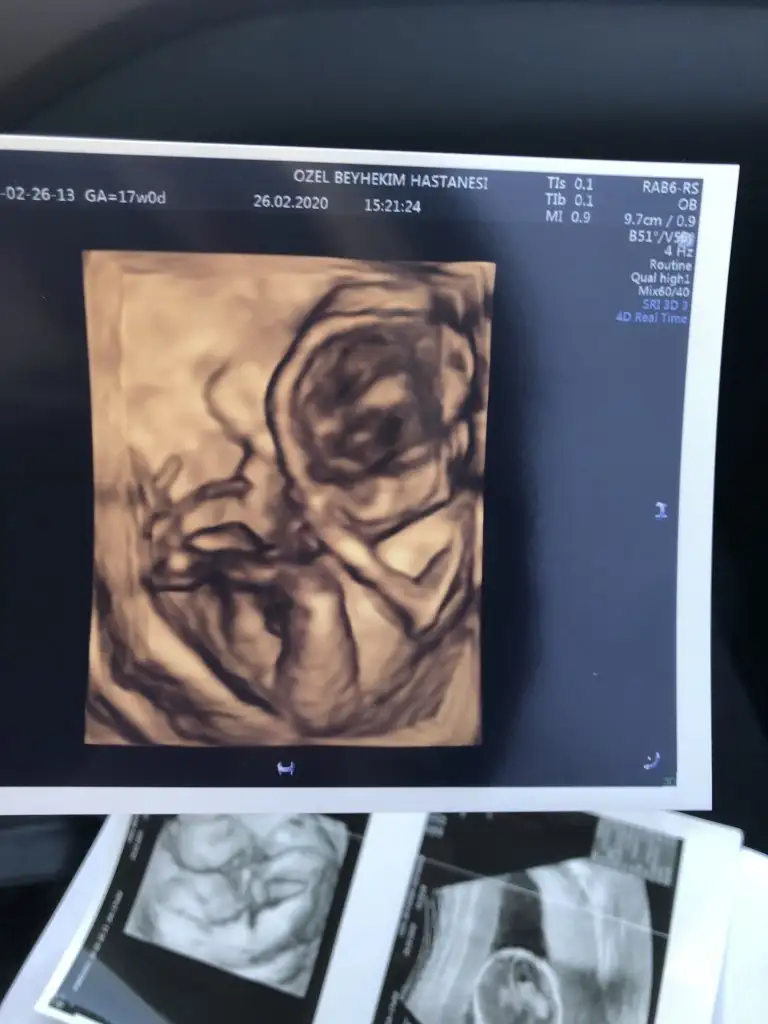

Maşallh bu minik kızçeye amaKızlar ben de bugün gitmek zorunda kaldım doktorabu da benim minik kızım ki doktor %100 kız dedi 16-17 cm 200gr kendisi 17+2 sat a göre tam 17 üçlü ya da dörtlü testi teklif dahi etmedi benim doktorum rahat diyorum detaylı da kendi bakacakmış ama belki yine de başka doktora da giderim

Kızlar ben de bugün gitmek zorunda kaldım doktorabu da benim minik kızım ki doktor %100 kız dedi 16-17 cm 200gr kendisi 17+2 sat a göre tam 17 üçlü ya da dörtlü testi teklif dahi etmedi benim doktorum rahat diyorum detaylı da kendi bakacakmış ama belki yine de başka doktora da giderim